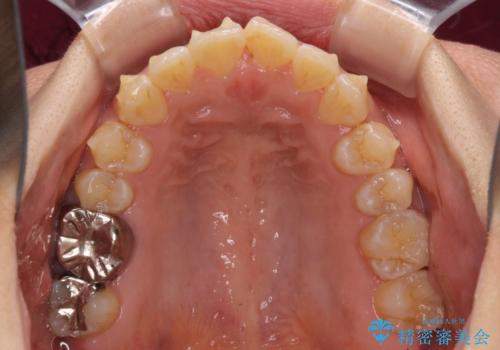

インビザラインによる狭窄歯列の拡大矯正

上下顎ともに歯列全体の後方移動と側方拡大、IPR(歯と歯の間を削る)によってデコボコが解消するように設計し、インビザラインにより治療を行うこととしました。

治療途中で関西に転勤となってしまったため、東京に出張で来るタイミングに合わせて治療を進めることになりました。そのため、治療期間が長くなってしまいましたが、無事に仕上げることができました。